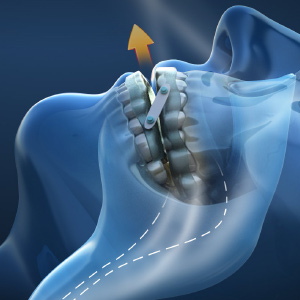

Grand Design: Implant and Full-Arch Solutions for Strength and Stability

Implant therapy has become an integral part of clinical dentistry, with ever-increasing numbers of patients seeking this treatment. However, this good news comes with a significant challenge: patients have increasing expectations for shortened treatment duration - even patients with anatomical deficiencies. You need serious treatment flexibility to create optimal outcomes for all indications. Learn more about advanced system options in this new eBook.